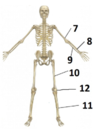

Namnge delarna

- humerus

- radius

- ulna

- femur

- tibia

- patella

Namnge de olika delarna.

- vertebra

- radius

- sternum

- humerus

- clavicula

- costae

- os coxae

- ulna

- falang

- os sacrum

- symfys

- patella

- talus

- trochanter major

- femur

- fibula

- tibia